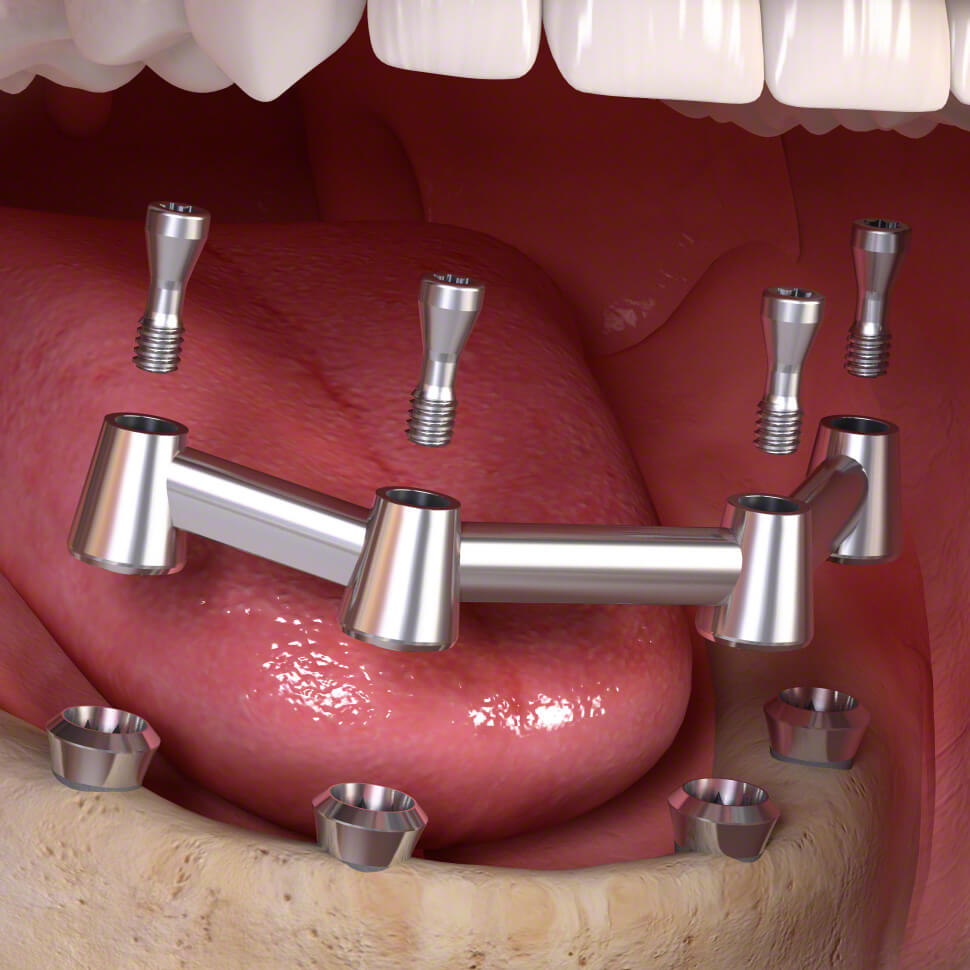

Az instabil műfogsorral kapcsolatos problémák szerencsére hatékonyan orvosolhatók a fix, implantátumokon rögzített kivehető fogsor különleges technológiájának segítségével. Ennek lelkét a kiváló minőségű titánból készült implantátumok jelentik.

A fix fogsor összetevői:

- különleges minőségű, extra stabilitást és tartósságot szavatoló titán implantátumok.

Erre egyrészt a már említett minőségi titán implantátumok és a Dentpoint munkatársainak kimagasló szaktudása, valamint a rendelőnkben elérhető fogorvosi csúcstechnika a garancia. Másrészt pedig a fix fogsor rögzítésére szolgáló, rendkívül alapos és hatékony szakmai eljárás, amely mind a felső, mind az alsó fogsor stabil és tartós rögzítését garantálja.

- A fog implantátum csavarok beültetése.

- Implantátumok felszabadítása és ínyformázás.

- A műfogsorba épített speciális rögzítőelemek a korábbinál nagyságrendekkel nagyobb stabilitást biztosítanak a fix fogsornak.